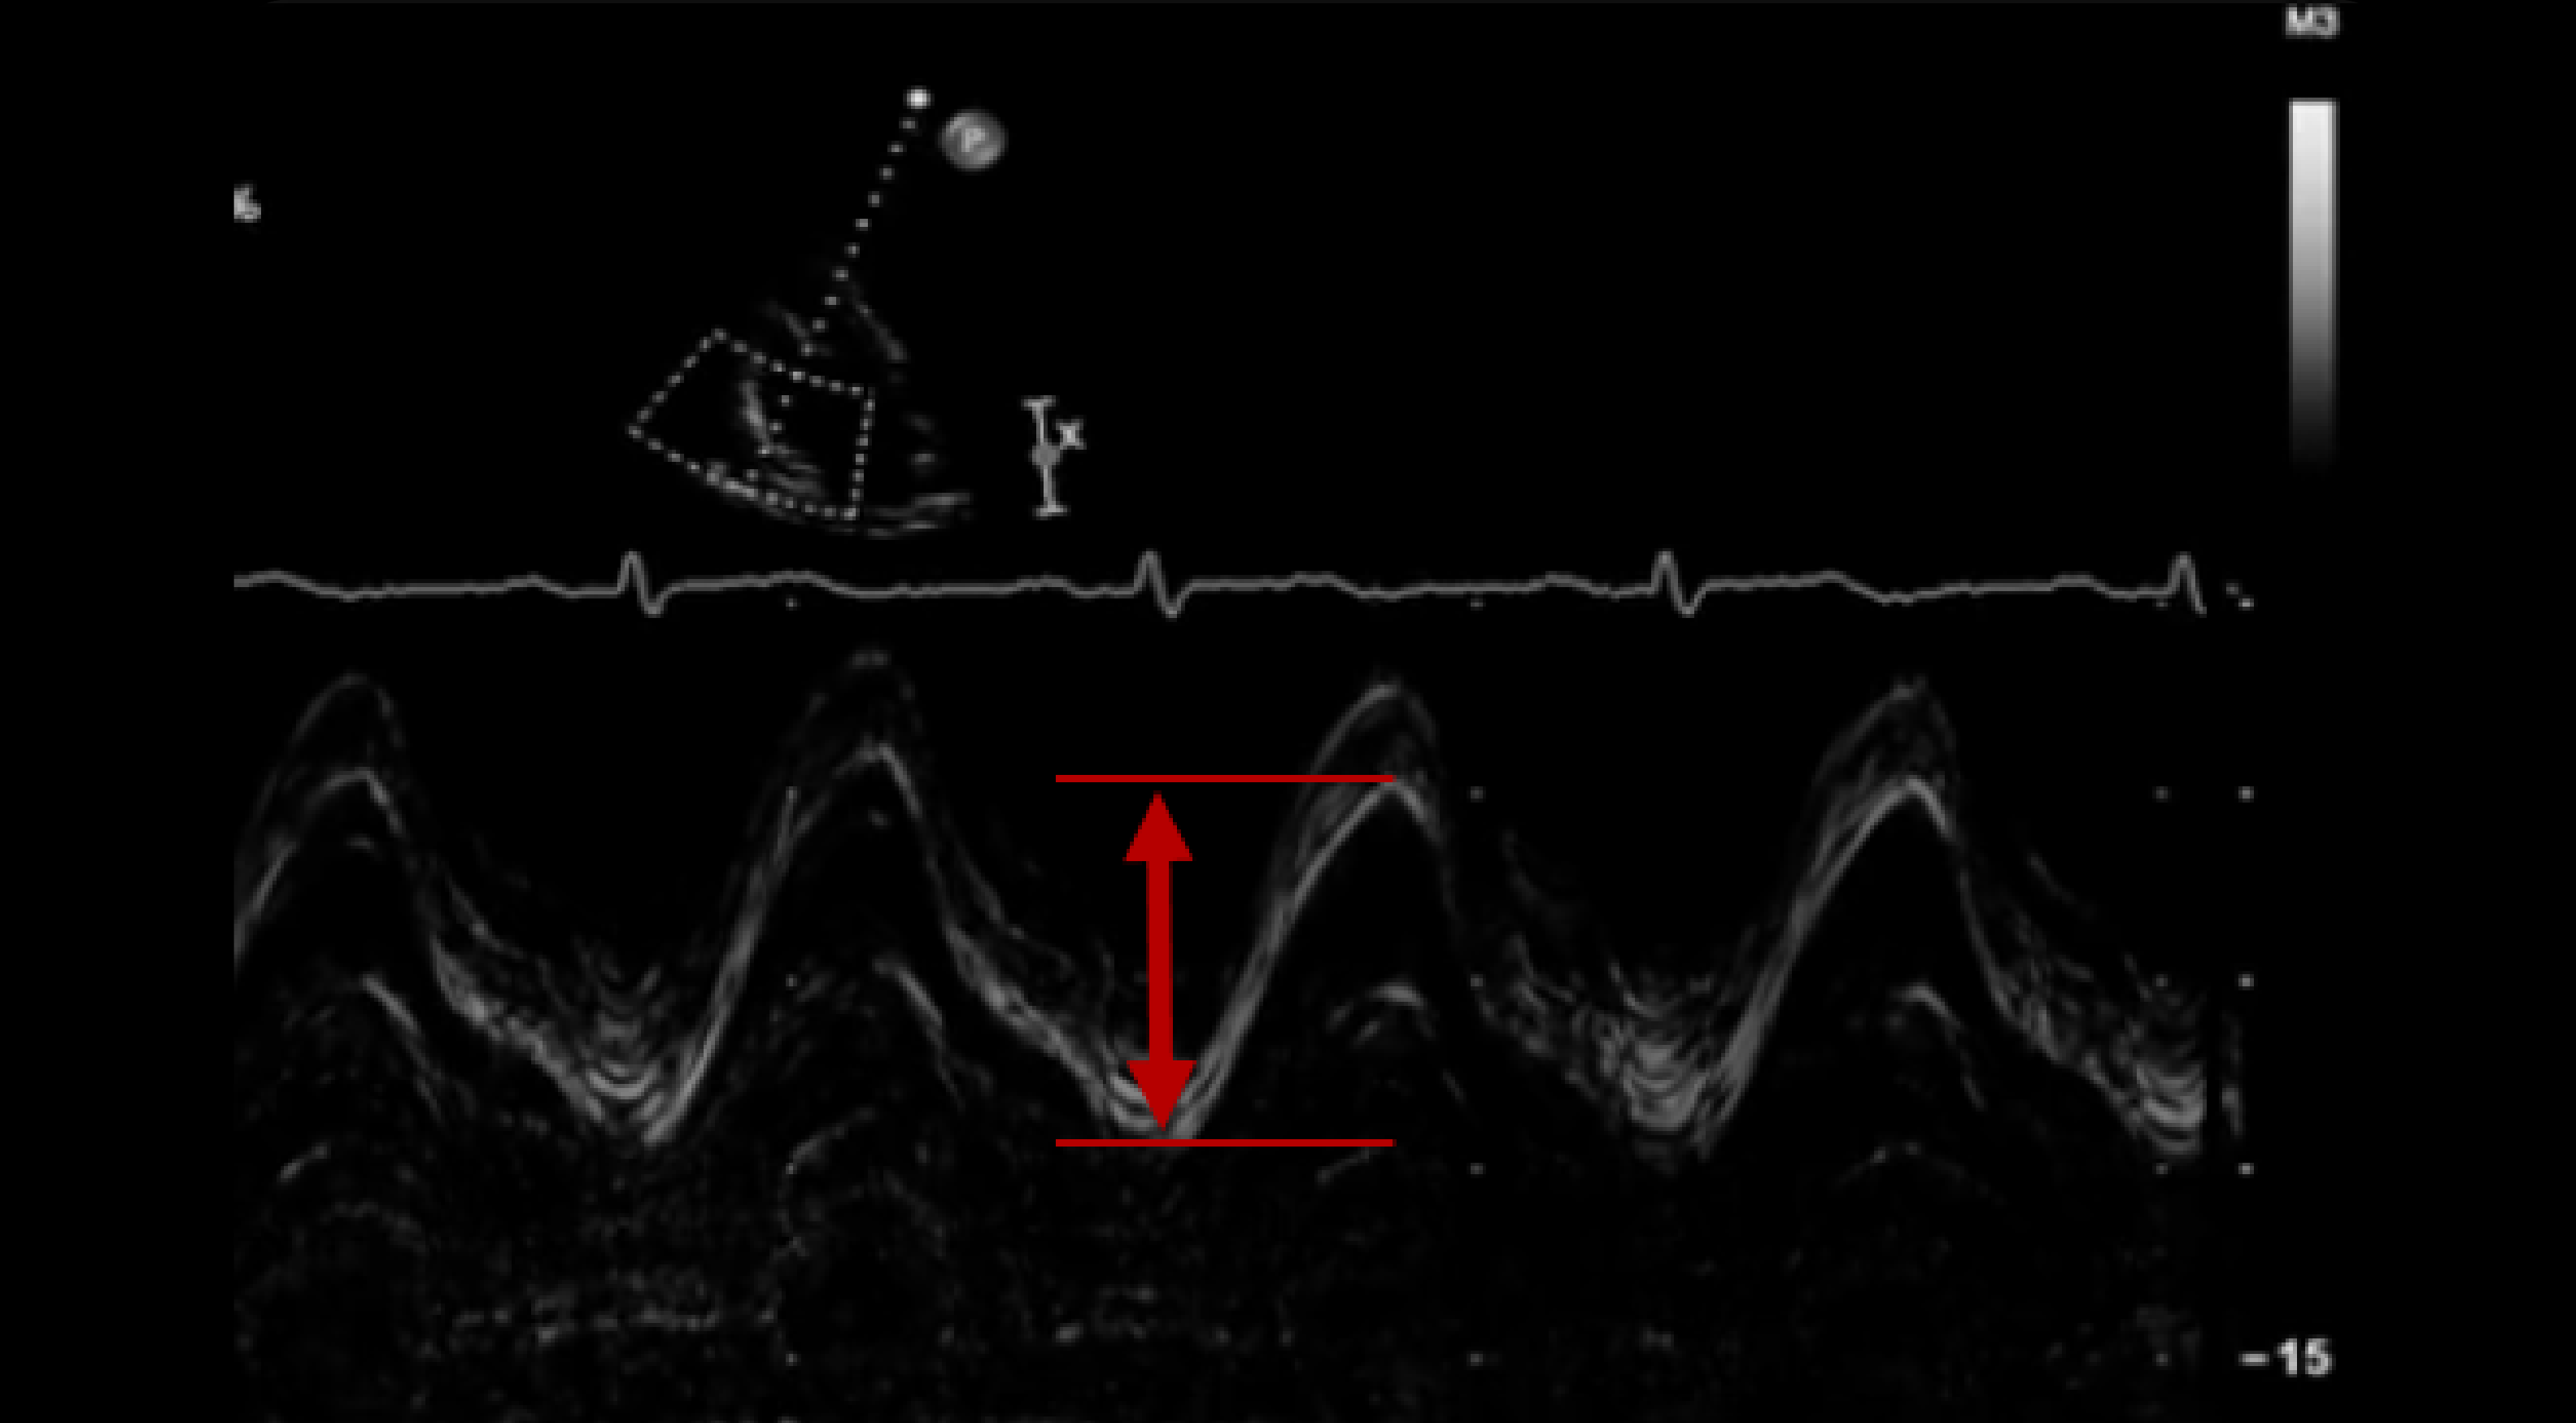

Representative echocardiographic images for the measurement of TAPSE. a

Measurement of tricuspid annular plane systolic excursion (TAPSE) TAPSE What Is A Normal Tapse Tricuspid annular plane systolic excursion (tapse) can provide a point of care ultrasound assessment of right ventricular function. It is considered among the most reliable tools to measure or. Describe the acoustic windows and echocardiographic views required for optimal evaluation of the right heart. Tapse (tricuspid annular plane systolic excursion) tapse is the best single indicator of rv systolic function. What Is A Normal Tapse.

Measurement of TAPSE in Mmode echocardiography. a TAPSE in apical What Is A Normal Tapse In the apical 4 view, align the. Tapse (tricuspid annular plane systolic excursion) tapse is the best single indicator of rv systolic function at the bedside. Tricuspid annular plane systolic excursion (tapse) refers to the systolic longitudinal displacement of the lateral tricuspid annulus. Normal function is restricted mainly to longitudinal (base to apex) shortening and systolic thickening systolic function: Tapse. What Is A Normal Tapse.

Representative echocardiographic images for the measurement of TAPSE. a What Is A Normal Tapse Tapse (tricuspid annular plane systolic excursion) normal is >1.7cm (less useful post some cardiac surgery) [measured in ap4c w/ m mode] Tapse (tricuspid annular plane systolic excursion) tapse is the best single indicator of rv systolic function at the bedside. Tapse measures the longitudinal movement of the lateral tricuspid annular plane during systole. Describe the acoustic windows and echocardiographic views. What Is A Normal Tapse.